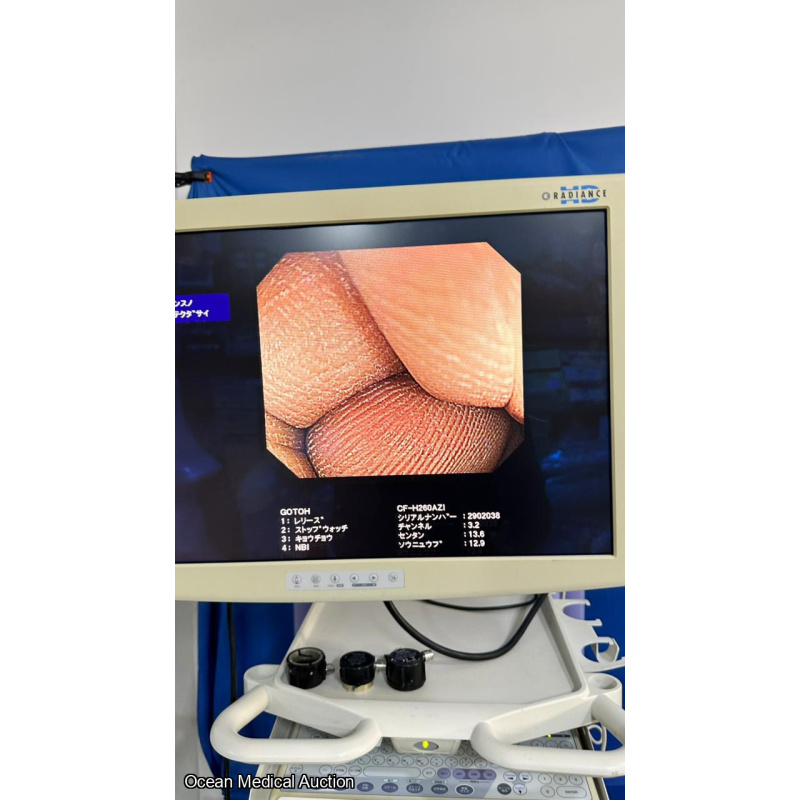

OLYMPUS CF-H260AZI SN.2902038 AND IT IS IN WORKING CONDITION